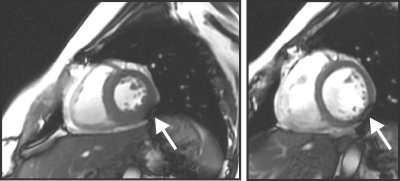

Cardiac functional scans adopting bSSFP sequences at 3 T suffer from dark band artifacts due to B0 inhomogeneity inside the human heart1, 2 (Figure 1). The most effective remedy to mitigate this issue is to homogenize the B0 distribution in the heart via B0 shimming3, typically achieved in MR scanners via spherical harmonic (SH) shim coils up to second- or third-order4. Mattar et al.5 theoretically accessed the potential of global SH shimming in the whole heart and dynamic shimming within local axial slices upon five in vivo B0 maps. Recent work at 7 T from Hock et al.6 compared experimental shim results of these types in the same orientation. Although both studies suggest better results for dynamic shimming, as expected, the associated shim performance on cardiac imaging planes, e.g., short-axis views, remains unknown. Furthermore, in vivo acquired B0 maps in these and other studies2, 4 are constrained by limited sample size, spatial resolution, and the number of slices due to short acquisition time under breath-hold conditions. The consequential limited knowledge of B0 conditions in cardiac imaging planes impedes the development of an optimal shim strategy. We recently presented a customized method for computing high-resolution cardiac B0 maps based on routine CT images7. Here we propose an oblique slicing method to obtain B0 distributions of short-axis views based on simulated B0 maps from a large and diverse population of human subjects. We analyze the B0 conditions in the heart with SH-based B0 shimming in clinically relevant slice orientations to set the stage for developing optimal B0 shim strategies tailored to cardiac MRI.

Fig. 1. Susceptibility-induced artifacts in the myocardium caused by B0 variations in the heart. In vivo cardiac cine images were acquired using a bSSFP sequence with a TR of 3.56 ms after a linear shim provided by the scanner at 3 T. Dark band artifacts (white arrow) are presented in the inferolateral wall of the myocardium in the systolic (left) and diastolic (right) cardiac phases. These artifacts were induced by off-resonance frequencies in the heart.